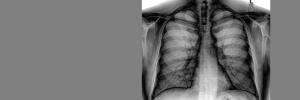

South Africa had the highest TB incidence in the world in 2016, with 781 per 100 000 population. TB is the country's leading cause of death.